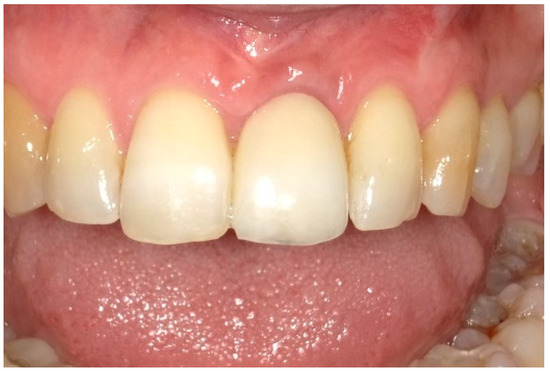

6. Follow-Up

7. Outcomes

| Midfacial mucosa level at Tpre (mm) | 3.0 | 2.0 | 5.0 |

| Midfacial mucosa level at T9 (mm) | 5.0 | 6.0 | 6.0 |

| Midfacial mucosa level at T12 (mm) | 5.0 | 6.0 | 6.0 |

| Mesial papilla | 1 | 1 | 0 | 0 | 2 | 2 |

| Distal papilla | 1 | 1 | 0 | 0 | 2 | 1 |

| Curvature of the facial mucosa | 1 | 1 | 2 | 2 | 1 | 2 |

| Level of the facial mucosa | 0 | 2 | 2 | 1 | 1 | 2 |

| Root convexity/soft tissue color and texture | 0 | 1 | 2 | 2 | 0 | 1 |

| Total | 3 | 6 | 6 | 5 | 6 | 8 |